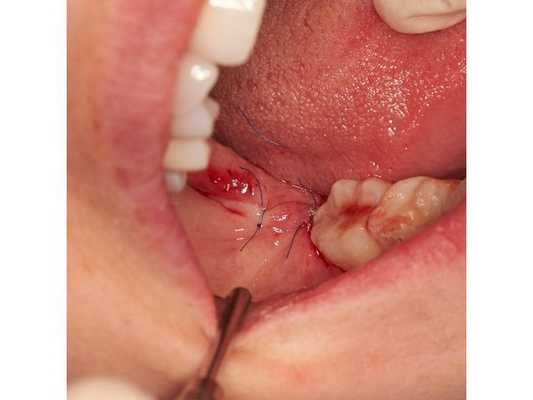

Зуб необходимо было удалить. Пациентке сделали проводниковую анестезию раствором убистезина ДС 1,7*2, выполнили разрез по вершине гребня от 48 до 46 зуба, лоскут отслоили. Корни 48 зуба были сегментированы (разделены на фрагменты путём отпиливания фрагмента коронки зуба) и удалены с помощью прямых элеваторов. Выполнен кюретаж (вычищение) раны, иссечение рубцовой ткани, антисептическая обработка 0,05 % раствором хлоргексидина. Рана заполнена губкой, пропитанной препаратом "Альвостаз". Выполнена мобилизация полнослойных лоскутов, герметичное ушивание раны с использованием нерезорбируемого (невпитывающегося) шовного материала монофил, повторная медикаментозная обработка 0,05 % раствором хлоргексидина. Оперативное вмешательство длилось 25 минут.

Через 12 часов отёк мягких тканей правой щеки увеличился, открывать рот стало ещё труднее, боли не было, температура поднялась до 37,0°C. К концу третьих суток отёк правой щеки стал максимально выражен, кожные покровы над областью вмешательства стали плотными, безболезненными при пальпации, цвет не изменился. Повышенная температура участка десны при этом является нормальным течением. К концу седьмых суток отёк спал. Рот пациентка открывает в меньшем объёме по сравнению с первичным обращением. Для улучшения результата лечения была назначена механотерапия — самостоятельное открывание рта пальцами до появления слабовыраженного болевого синдрома. Через 14 суток после операции слизистая полости рта эпителизировалась (зажила) полностью. Швы состоятельны. Слизистая бледно розового окраса, умеренно увлажнена. Выполнена антисептическая обработка полости рта и швов. Сами швы сняты, даны рекомендации по гигиене полости рта.